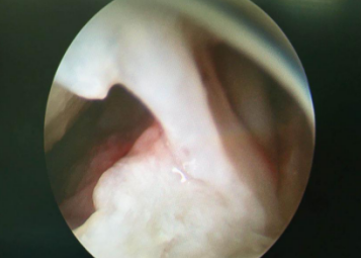

当天,冯大爷办理了住院手续,然后做了术前的相关检查,明确了诊断之后,齐伟亚主任、熊祖国医生和吴衡医师就在臂丛麻醉下为冯大爷在关节镜辅助下做了左腕囊肿切除术,术中探查囊肿蒂部位于舟月关节韧带背侧缘,术中分离囊肿四周直达底部,使用一次性刨刀切除囊肿蒂部及部分增生滑膜,背侧按压囊肿吸引囊液至清晰,生理盐水冲洗干静;手术进行的非常顺利,整个过程只用了30分钟,最重要的是,手术只在左腕背侧留下了两个3mm左右的切口。术后皮内各缝合1针,无需拆线。术后冯大爷非常满意,第二天给冯大爷换了药,就出院了。

术中探查